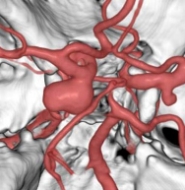

治療前

治療後

物が二重に見えるようになって発症した内頚動脈大型動脈瘤(矢印)の症例です。クリッピング術で直接動脈瘤をつぶすことができないため、バイパス術(矢印)を増設し内頚動脈を遮断することで動脈瘤を治療しました。